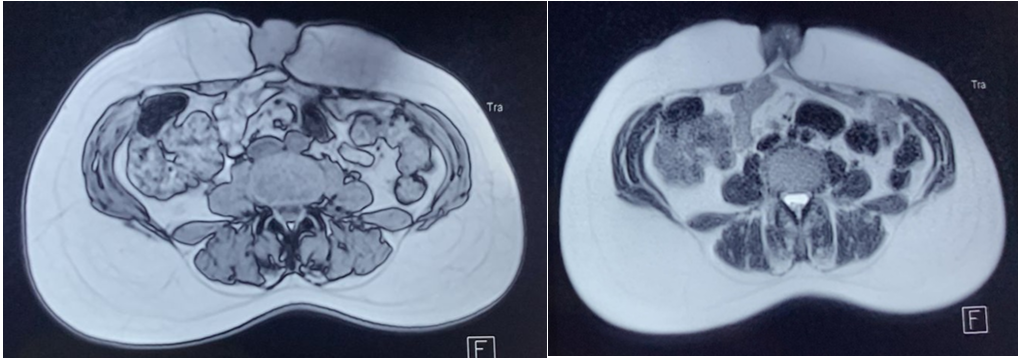

The surgical procedure involved resection of the mass (figure 5), with pathological examination revealing a polypoid congestive lesion with a congestive, lobulated surface, the site of haemorrhagic and fibrous remodelling, and comprising regularly lined endometrial glandular structures with no cytonuclear atypia, surrounded by a cytogenic stroma with no signs of malignancy, all in favour of parietal cutaneous endometriosis with no signs of malignancy.

Figure 5: Wide excision of the umbilical mass